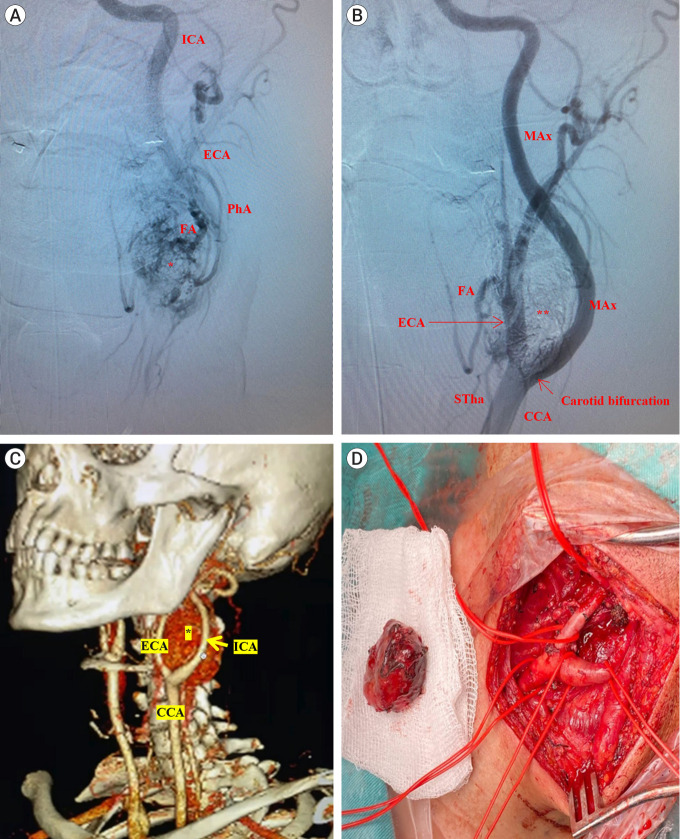

Methods: A literature review was conducted using PubMed, Scopus, and Web of Science databases with keywords related to preoperative embolization and highly vascularized tumors, detailing its definition, indications, diagnostic considerations, procedural aspects, clinical and surgical implications, and associated complications. The findings are supported by data from 309 patients with brain, head, and neck tumors treated with preoperative embolization at Hospital Clínica Kennedy in Guayaquil, Ecuador, from 2015 to 2023. Cases without embolization or those below the clavicular border were excluded. Illustrations and photographs, based on the authors' surgical experience, are included with informed consent.